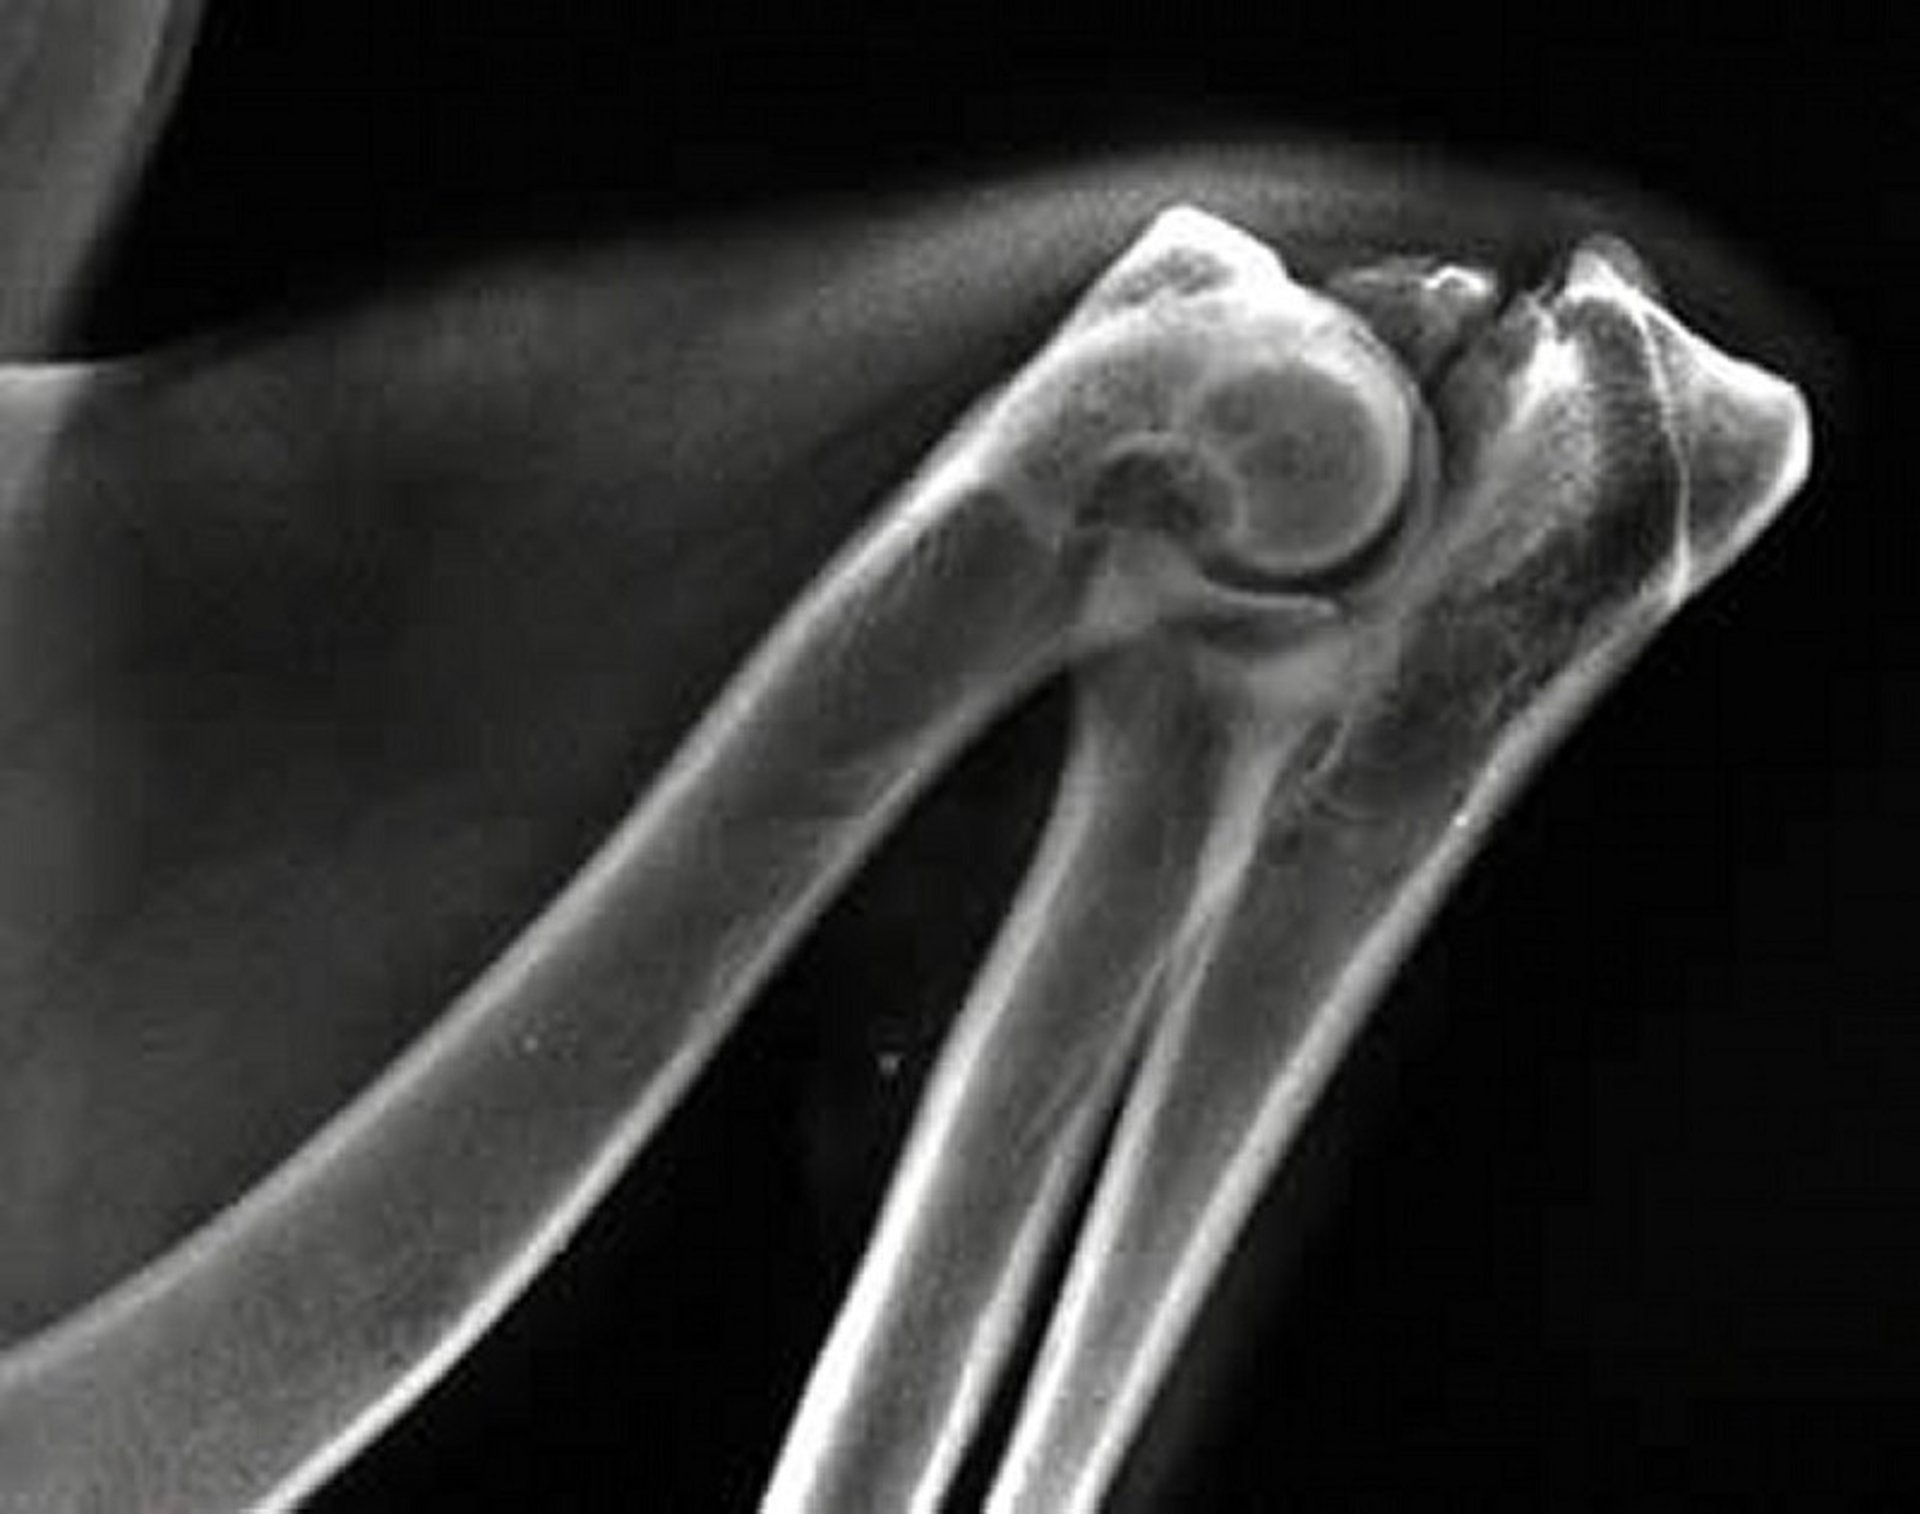

Diagnosis of MCD is based on imaging such as radiography, CT, or arthroscopy (see MCD image). CT is particularly useful for detecting subtle lesions.

Medial coronoid disease (MCD) is one of the most common manifestations of elbow dysplasia in dogs. MCD is a spectrum of developmental abnormalities affecting the medial coronoid process of the ulna. These abnormalities occur most frequently in young large- and giant-breed dogs, such as Labrador Retrievers, Golden Retrievers, Bernese Mountain Dogs, and Rottweilers.

MCD includes conditions such as fragmentation of the medial coronoid process (FMCP), cartilage erosion, fissures, or abnormal shape or size of the coronoid. These lesions result from osteochondrosis, abnormal joint development, and incongruity between the radius and ulna, leading to excessive mechanical loading of the medial compartment of the elbow.

Dogs with MCD often show forelimb lameness, stiffness after rest, decreased range of motion, joint effusion, and pain on elbow manipulation.